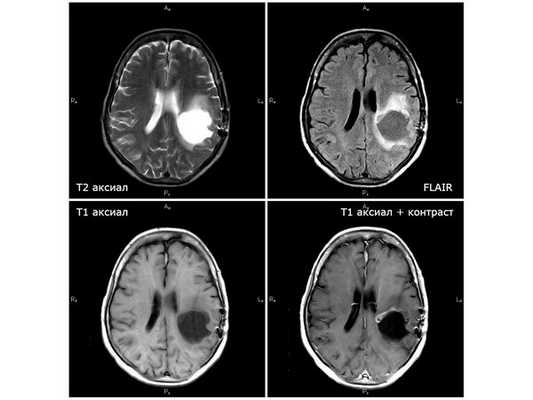

НАЧАЛО ЛЕЧЕНИЯ На базе нейрохирургического отделение больницы с 11.08.18 по 25.08.18 была проведена противоотёчная и симптоматическая терапия. По результатам ЭЭГ (электроэнцефалографии) от 13.08.18, признаков пароксизмальной активности (ухудшения) на момент исследования нет. Чтобы решить вопрос об оперативном лечении, 25.08.18 пациентку направили на консультацию нейрохирурга в областную клиническую больницу Белгорода. Оттуда её госпитализировали в московский центре нейрохирургии им. ак. Н.Н.Бурденко. Там пациентка находилась на стационарном лечении с 29.08.18 по 04.09.18. 30.08.18 национальном медицинском центре ей провели операцию: удалили внутримозговую опухоль левой теменной доли с использованием УЗ-навигации и нейрофизиологического мониторинга проводящих путей. Исследования опухолевой ткани показали, что удалённая опухоль является глиобластомой — высокозлокачественной астроцитарной опухолью без выявленной мутации IDH1 R132H. По результатам послеоперационной КТ без контрастирования, ишемических и геморрагических осложнений не выявлено, остатки опухоли не обнаружены. Послеоперационный период протекал удовлетворительно. На следующий день пациентка уже могла находиться в вертикальном положении, сила в правых конечностях увеличилась, что говорило о положительной динамике. Пациентке было рекомендовано наблюдаться у невролога, онколога и сосудистого хирурга по месту жительства, проконсультироваться с радиологом и химиотерапевтом центра нейрохирургии. Учитывая природу опухоли, клиническую картину и данные исследований, женщине рекомендовано пройти курс лучевой терапии. Начинать его можно было в течение 1-4 недель после проведённой операции. ХИМИОЛУЧЕВАЯ ТЕРАПИЯ: рекомендации Лечение было комбинированным: радиотерапия на ложе опухоли до суммарной дозы (СОД) 60 гр с одновременным приёмом темозоломида в дозе 75 мг/кв. м. Рекомендуемая доза препарата на весь период лучевой терапии — 120 мг/сут. Темозоломид показано принимать внутрь натощак за два часа до приёма пищи, запивая водой (в дни проведения радиотерапии — за 0,5-1,5 часа до сеанса), по одной капсуле 100 мг и одной капсуле 20 мг либо 100 мг/сут ежедневно без перерыва на выходные. При возникновении тошноты на фоне лечения рекомендовано за 30 минут до приёма темозоломида натощак принимать 4 мг ондансетрона. Через три недели после завершения радиотерапии требуется выполнить МРТ с контрастированием и повторно проконсультироваться в центре нейрохирургии им. Н.Н. Бурденко для дальнейшего плана химиотерапии. Следующий этап химиотерапии планируется продолжить через 28 дней после завершения комбинированного лечения. При стабильной картине МРТ и удовлетворительных показателях крови приём темозоломида в дозе 200 мг/кв. м нужно будет продолжить в другом режиме: рекомендуемая доза — 300 мг, принимать ежедневно внутрь в течение пяти дней с последующим перерывом в 23 дня. В целом запланировано 6-10 курсов химиотерапии с дальнейшим решением вопроса о необходимости продолжения лечения. НАЧАЛО ХИМИОЛУЧЕВОЙ ТЕРАПИИ Первый этап химио- и радиотерапии проводился на базе Белгородского онкологического диспансера около месяца — с 19.09.18 по 12.10.18. Лечение предполагало лучевую терапию с суммарной лучевой дозой 30 гр. на фоне приёма 100 мг темозоломида за час до сеанса облучения. В результате лечения состояние пациентки стабилизировалось, неврологический статус не страдал. Лучевые реакции выражены умеренно. Рекомендовано: ⠀•⠀наблюдаться у онколога и невропатолога; ⠀•⠀при необходимости пройти противоотёчную терапию; ⠀•⠀ограничить физические и эмоциональные нагрузки; ⠀•⠀через три недели при отсутствии противопоказаний продолжить лучевую терапию с госпитализацией в Белгородский онкологический диспансер. Через две недели после химиолучеовй терапии 30.10.2018 проведено контрольная МРТ: снимки показали феномен псевдопрогрессии с увеличением поперечной дислокации и нарастанием отёка вокруг опухоли. Примерно через месяц после завершения первого этапа лучевой терапии усилились головные боли и стала нарастать общая слабость. В связи с этим с 06.11.18 по 16.11.18 пациентка находилась на стационарном лечении в нейрохирургическом отделении городской больницы № 1 г. Старый Оскол. Получала осмотерапию, лёгкую дегидратацию, кортикостероидные и гастропротективные (противоязвенные) препараты. Выписана в удовлетворительном состоянии. Рекомендовано принимать дексаметазон по 25 мг три раза в день. Спустя семь недель после химиолучевой терапии 21.11.18 проведена ещё одна контрольная МРТ: наблюдается положительная динамика с уменьшением объёма опухоли, поперечной дислокации и отёка вокруг опухоли. ВТОРОЙ ЭТАП ХИМИОЛУЧЕВОЙ ТЕРАПИИ Для проведения второго этапа лучевой терапии пациентка госпитализировалась в Белгородский онкологический диспансер. Там она находилась с 26.11.18 по 14.12.18. Проведена лучевая терапия на ложе опухоли головного мозга с суммарной очаговой дозой 30 гр. Общая суммарная доза за второй этап составила 60 гр. Ежедневно перед сеансом облучения пациентка принимала 100 мг темозоломида. Рекомендовано: ⠀•⠀наблюдаться и проходить лечение у онколога и невролога по месту жительства; ⠀•⠀прийти на контрольный осмотр в поликлинику Белгородского онкологического диспансера через два месяца.

По данным МРТ головного мозга, в течение четырёх месяцев от начала лучевой терапии отмечался период улучшения. Однако несмотря на проведённый второй этап лучевой терапии болезнь стала прогрессировать: по данным контрольной МРТ от 08.02.19, появились дополнительные опухолевые узлы, рост глиобластомы продолжился. 25.02.19 пациентка в экстренном порядке поступила в нейрохирургическое отделение городской больницы № 1 г. Старый Оскол с подозрением на острое нарушение мозгового кровообращения с нарастанием правостороннего гемипареза (поражения руки и ноги справа) и нарушением речи. Находилась там на стационарном лечении до 07.03.19. Жалоб не предъявляла по причине тяжёлого состояния. Проведено лечение: внутривенное введение эуфиллина, поляризующей смеси, фуросемида и дексаметазона. Нарушение речи купировано, гемипарез значительно регрессировал. Выписана в относительно удовлетворительном состоянии. Назначен приём дексаметазона по 25 мг три раза в день. По данным МРТ от 26.02.19, отрицательная динамика стремительно нарастала: увеличивался отёк, появившиеся узлы вокруг опухолевой кисты увеличились в два раза.